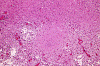

A 5 year-old Boy with Nausea and Vomiting for Three Months.

These photos were obtained from the formalin fixed paraffin embedded sections.